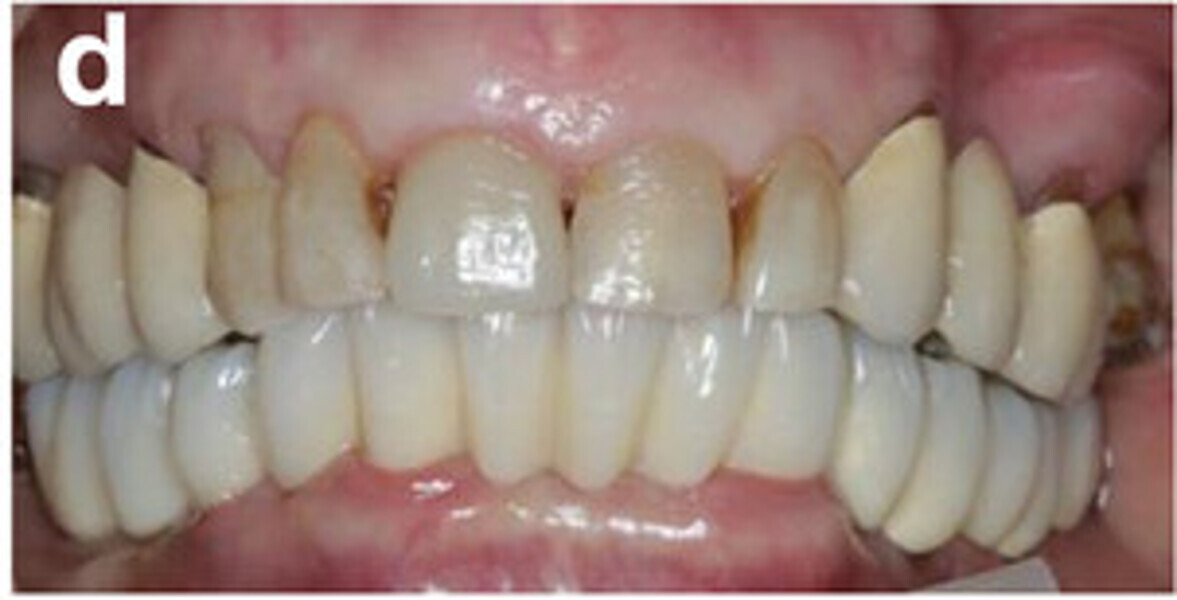

Fig. 14a: Occlusal, frontal and lateral views on the day of delivery, showing healthy peri-implant mucosal conditions (a) and the final CAD/CAM restoration in situ (b–e).

Fig. 14b: Occlusal, frontal and lateral views on the day of delivery, showing healthy peri-implant mucosal conditions (a) and the final CAD/CAM restoration in situ (b–e).

Fig. 14c: Occlusal, frontal and lateral views on the day of delivery, showing healthy peri-implant mucosal conditions (a) and the final CAD/CAM restoration in situ (b–e).

Fig. 14d: Occlusal, frontal and lateral views on the day of delivery, showing healthy peri-implant mucosal conditions (a) and the final CAD/CAM restoration in situ (b–e).

Fig. 14e: Occlusal, frontal and lateral views on the day of delivery, showing healthy peri-implant mucosal conditions (a) and the final CAD/CAM restoration in situ (b–e).